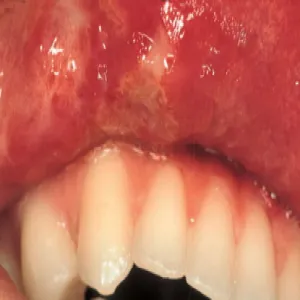

Choroba Behçeta